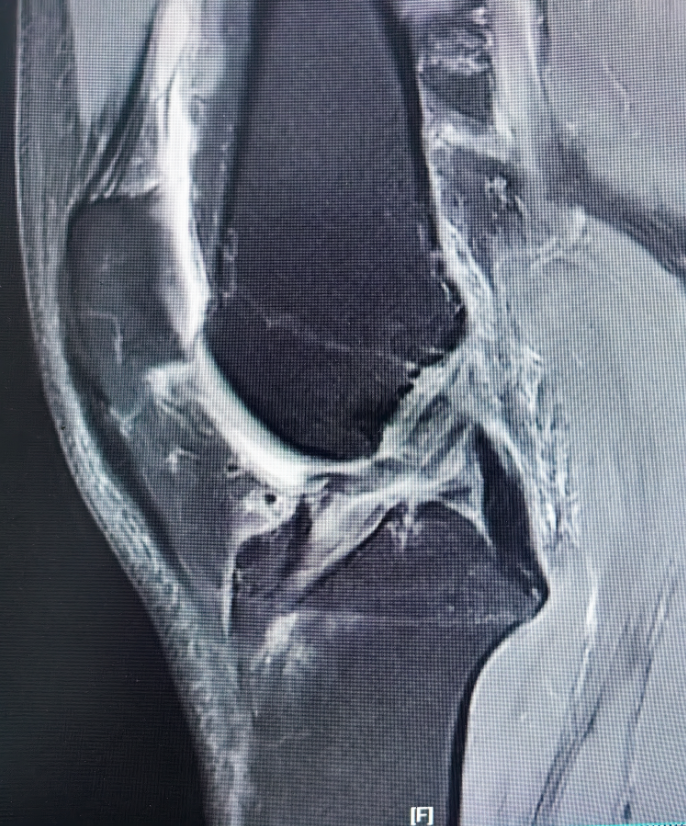

▲左膝MRI术前影像